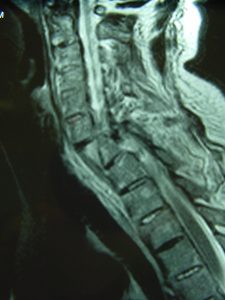

Εικόνα 2 (α,β,γ,δ,ε) Προεγχειρητική Μαγνητική Τομογραφία Α.Μ.Σ.Σ. – Ακολουθία Τ2 και Τ1 Οβελιαία τομή (Sagittal) λίγες ώρες μετά το ατύχημα. Η βλάβη ξεκινά από οπίσθια συνδεσμο-οστικά στοιχεία στο επίπεδο Α6-Α7 και περνά προσθίως μέσα από τον Μεσοσπονδύλιο Δίσκο και την πρόσθια κολόνα του 7ου αυχενικού σπονδύλου. Παρατηρείται μετατραυματικό οίδημα του νωτιαίου μυελού στο σύστοιχο επίπεδο.